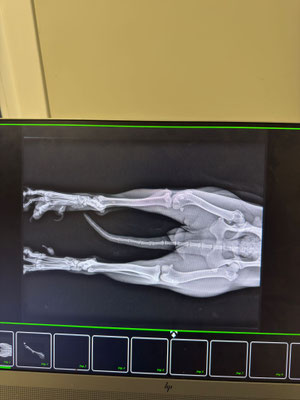

Sie hat Verletzungen an den Hinterbeinen